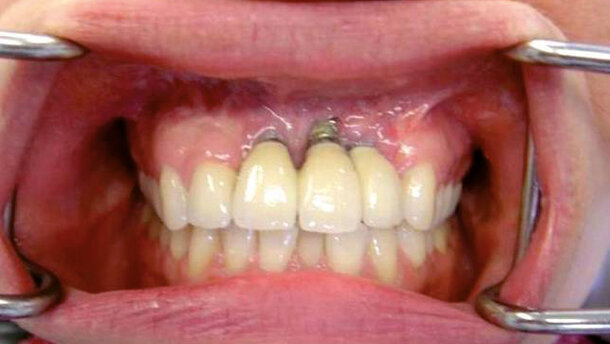

Una delle complicanze più comuni e temute nell’ambito di un trattamento implantare è la perimplantite (Fig. 1) che, se non trattata, solitamente porta alla perdita dell’impianto.

Inizialmente, la malattia dei tessuti perimplantari si manifesta come una mucosite, con progressiva perdita ossea nell’area implantare, come descritto da Albrektsson e collaboratori. Le cause di questa forma di malattia sono complesse e sono state proposte diverse ipotesi sullo sviluppo delle perimplantiti, tra cui un’insufficiente igiene orale, la mancanza di gengiva aderente e/o il sovraccarico implantare.